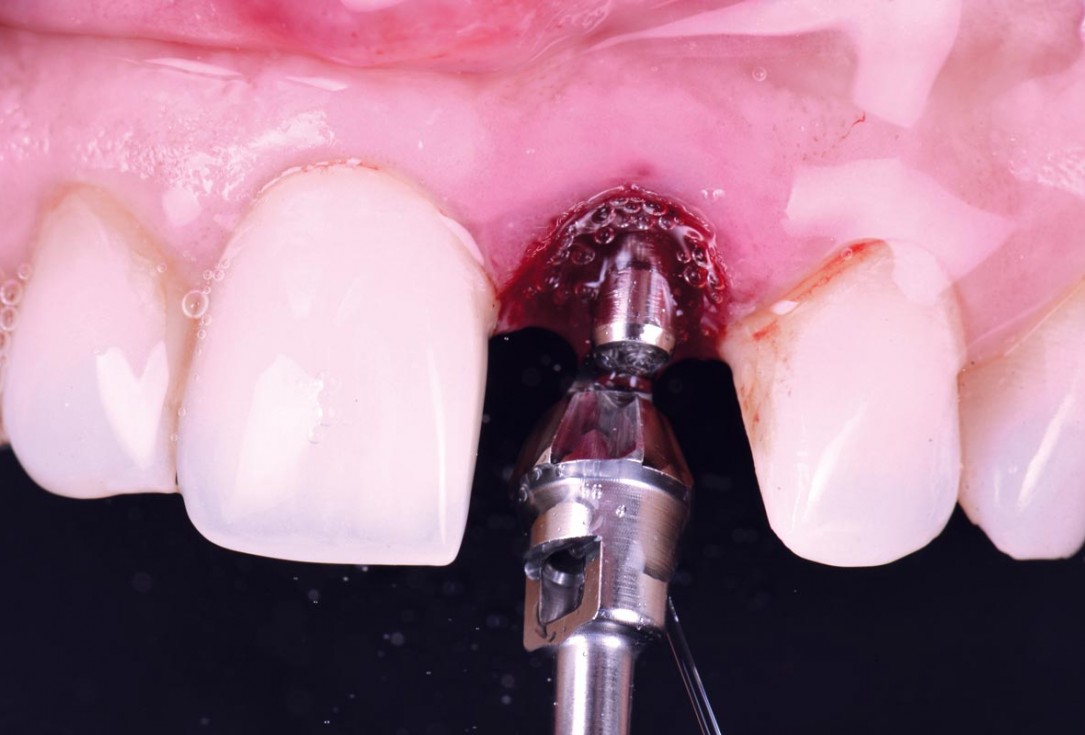

Initial clinical situation - Central incisors with dental destruction and periapical pathology